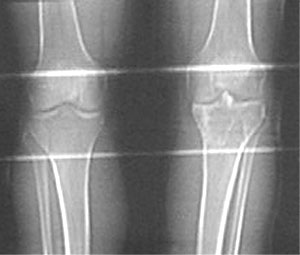

Auf dem Übersichtsbild ist schon mal sichtbar, was zu tun ist:

Nebst den verheilten Bruchstellen ist im verletzten linken Knie (rechts im Bild) auch die verknöcherte Eminenz (höchster Teil des Schienbeins im Kniegelenk) in der Mitte des Gelenks sichtbar. Diese ist deutlich zu hoch eingewachsen und verhindert die Streckung des Beins. Diesen Teil muss man im Rahmen einer Osteotomie versetzen: "ausschneiden", herunterziehen, einschrauben. Dieser Eingriff findet wahrscheinlich durch den Schienbeinknochen hindurch statt, um das Gelenk zu schonen und nicht nochmals vollständig öffnen zu müssen. Dazu wird versucht, Verklebungen in der Gelenkkapsel zu lösen und die unterdessen etwas verkürzten Muskeln und Bänder zu spannen.

Dazu als Vergleich das CT von zwei Tagen nach dem Unfall (15.4.2001), wo das ausgebrochene und in der ersten Operation reponierte Knochenstück schön sichtbar ist: